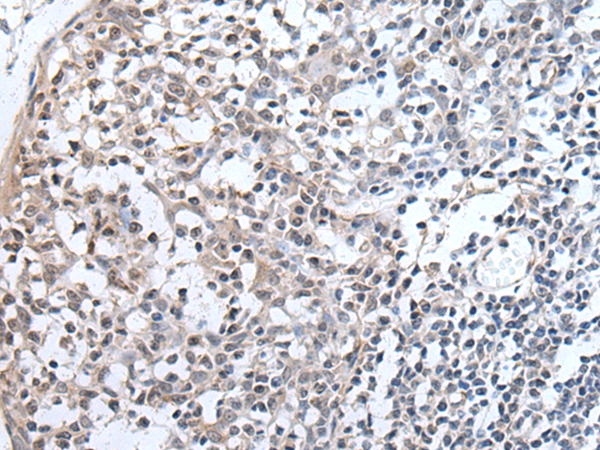

分类: 科研抗体货号: P12808别名: OX; PPOX; NRCLP1应用: IHC反应种属: Human, Mouse, Rat